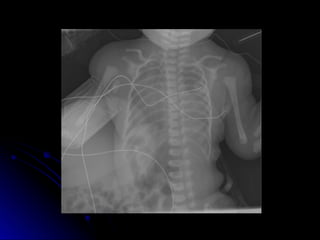

 Esophageal atresia with TEF is most

Esophageal atresia with TEF is most

common (85%).

Diagnosis may be suspected antenatal with

Diagnosis may be suspected antenatal with

absence of stomach bubble and

polyhydramnios. (*Caution: also seen with

conditions that lead to poor swallowing)